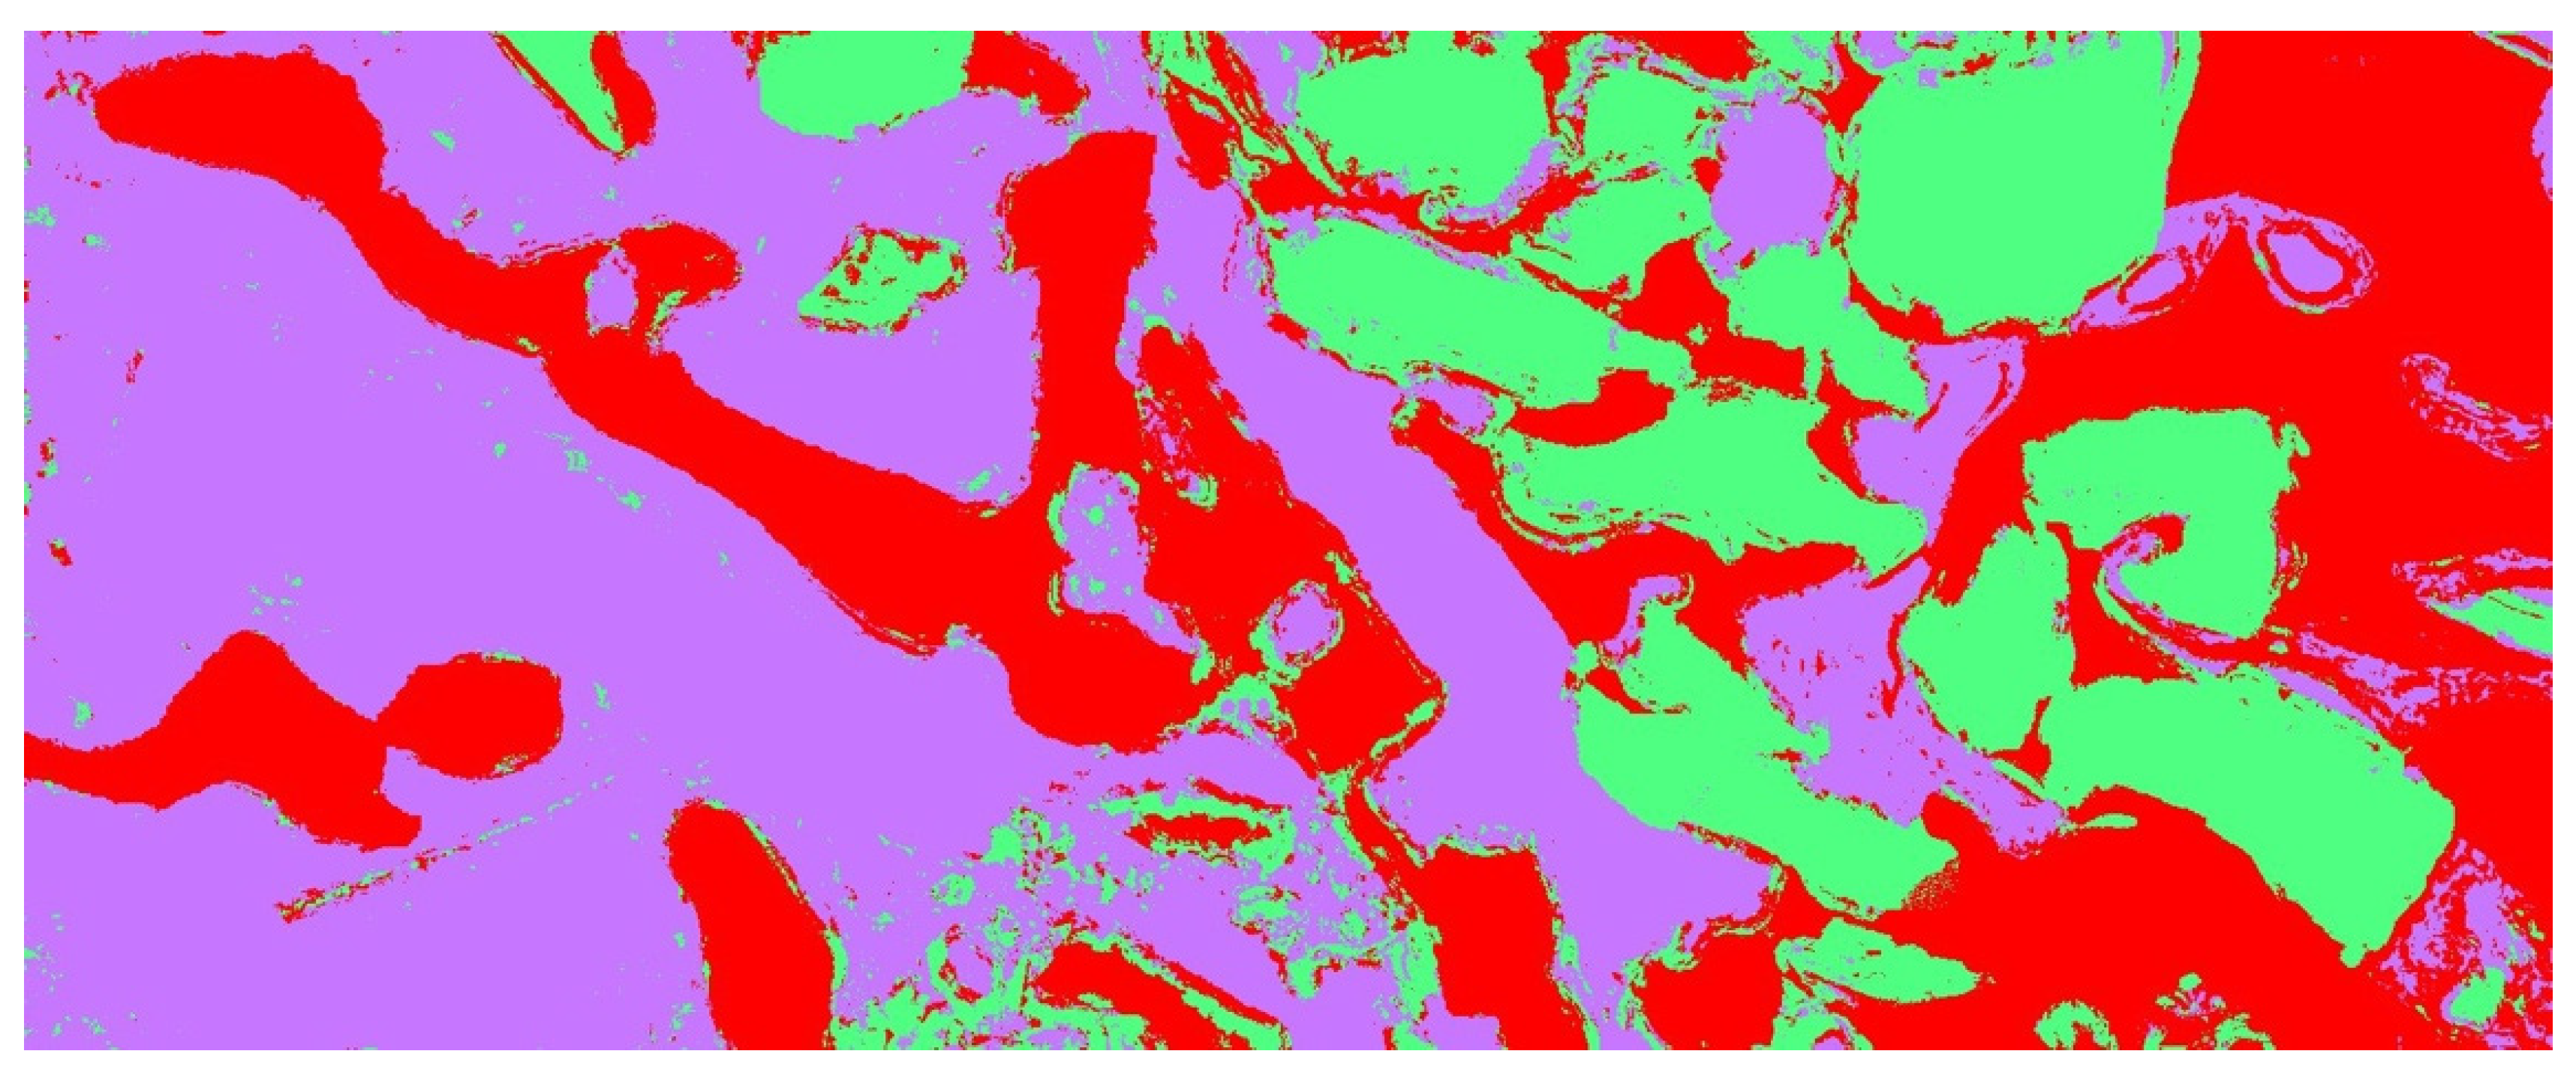

| NFB | RB | SF | |

|---|---|---|---|

| Mean % ± Std dev | 28.27 ± 10.62 | 10.39 ± 12.01 | 61.33 ± 12.08 |

| Range % (Min-Max) | 16.51–59.74 | 0–36.89 | 40.26–75.59 |